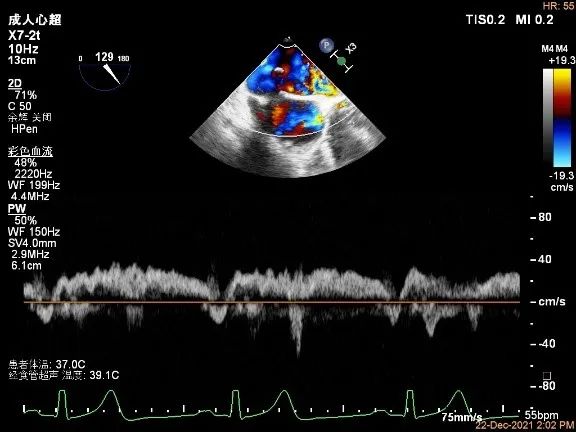

肺静脉血流频谱恢复正向趋势

肺静脉血流频谱完全恢复正向